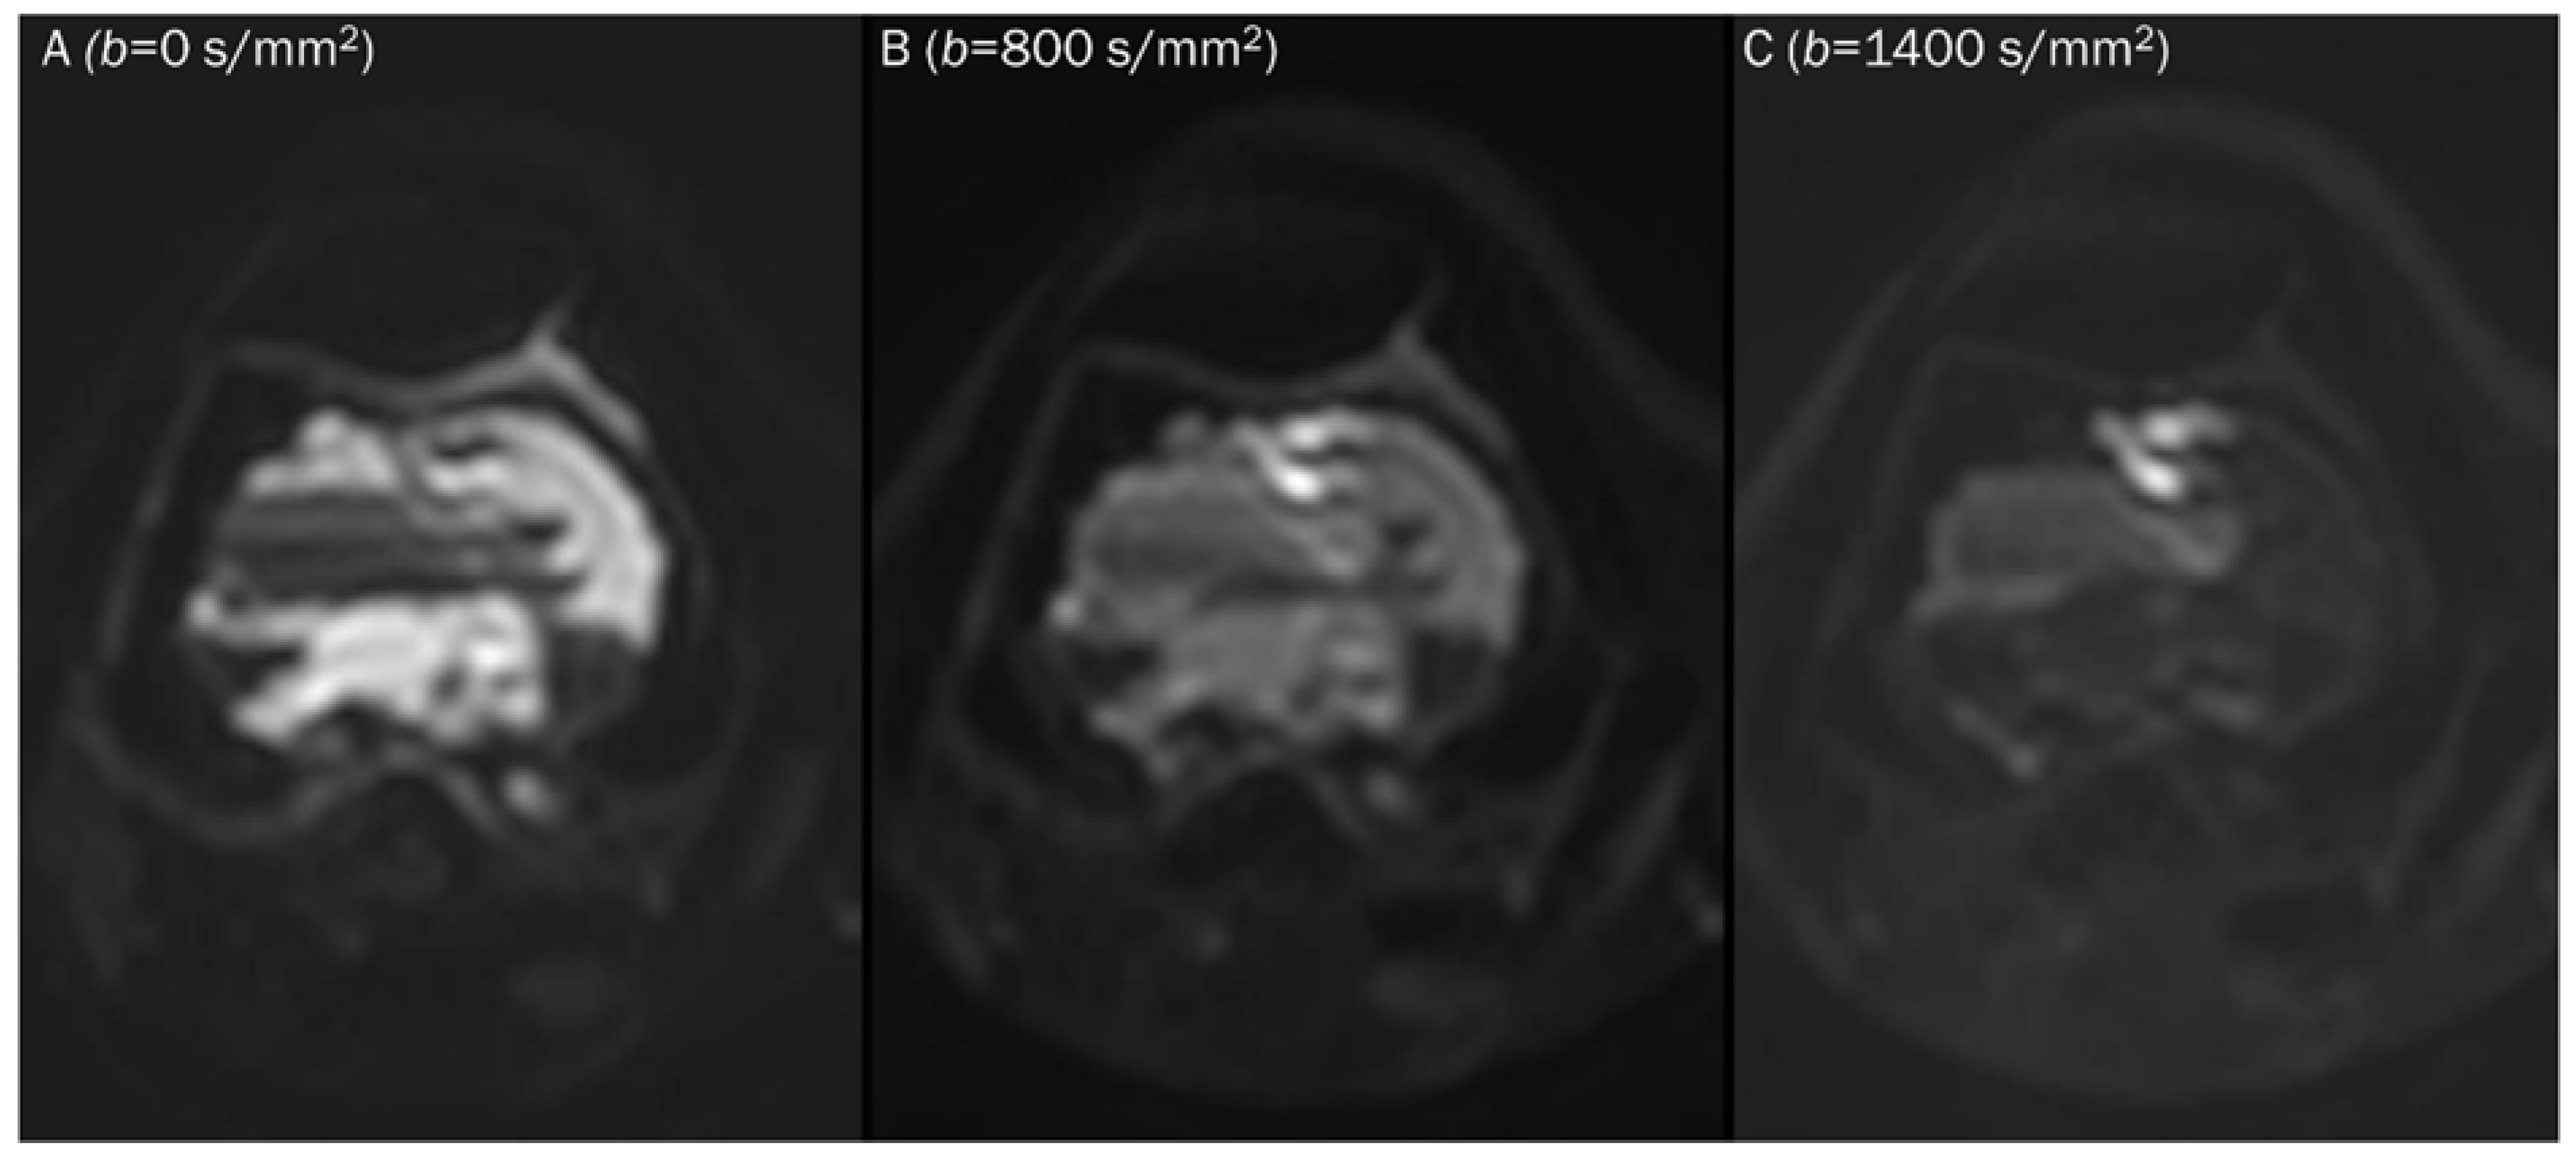

7.2. Hematoma

- Subhawong, T.K.; Durand, D.J.; Thawait, G.K.; Jacobs, M.A.; Fayad, L.M. Characterization of soft tissue masses: Can quantitative diffusion weighted imaging reliably distinguish cysts from solid masses? Skelet. Radiol. 2013, 42, 1583–1592. [Google Scholar] [CrossRef]